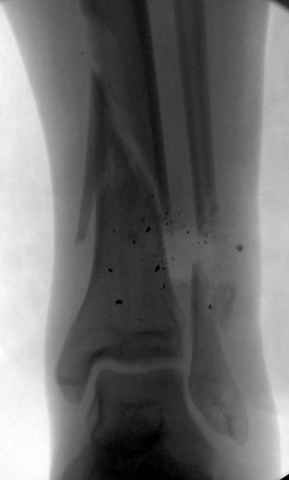

На снимках варианты фиксации малоберцовой:

№ 1 двух лодыжек

№ 2-5 при огнестрельном переломе